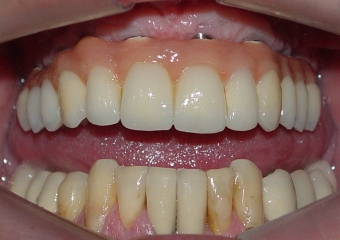

Prótese fixa em porcelana superior

Sorriso do caso terminado em abril de 2012